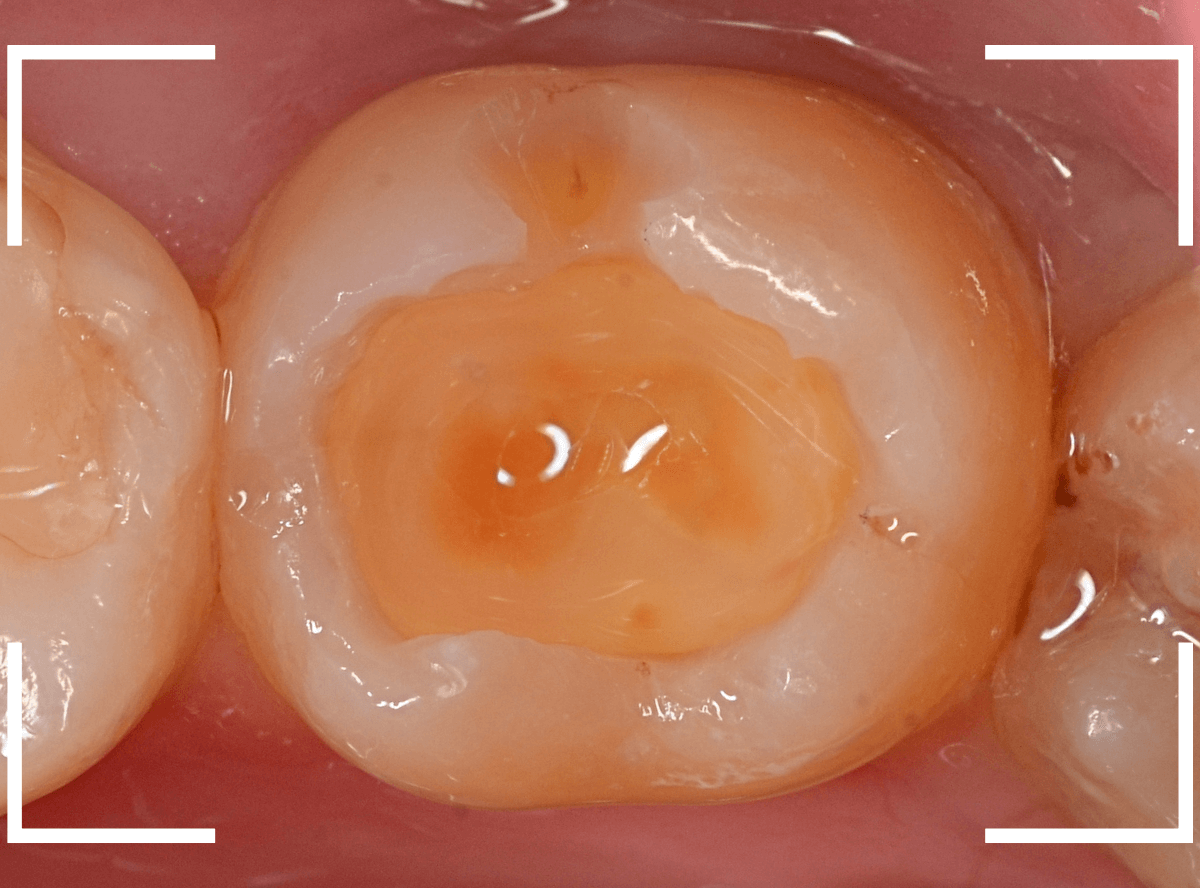

Case.20 劣化したレジン側面から進行した虫歯

「つめものが欠けたまま長期間放置して、歯がしみる」という訴えで来院された患者さんさんです。

拝見すると、劣化したレジンが欠けて、中で虫歯になっているのがわかります。

・欠けたまま長期間放置した

・しみるという自覚症状がある

事から、中で深い虫歯になっている事が想像されます。

レントゲン写真で確認します。

赤い線がレジンが入っている部分。

青い線が歯の神経です。

かなり神経の近いところまでレジンがつめてあるのがわかりますが、虫歯が側面からどの程度進んでいるのかはよくわかりません。

レントゲン写真だけみると、治療の必要がなさそうにも見えます。

このように、初見では虫歯になっている事が明らかなのに、レントゲン写真ではまったくわからないとう事もあります。

レジンを外しながら、虫歯を確認します。

慎重にレジンを除去しましたが、途中で露髄(神経が露出する事)しました。

歯の神経の中には、血管も含まれているので、神経が露出すると、このように出血します。

「しみる、痛い」などの明確な強い症状がある場合、このような状況の事が多いです。

今回は出血量が多く、神経を除去する治療(抜髄)の可能性が高いとも感じましたが、できる限り神経を保存する方法を取ることにしました。

神経を保護するお薬をつめて蓋をしてしばらく経過観察します。

神経を除去すると、治療期間が長引くうえに、歯の寿命がとても短くなってしまいます。

できるだけ歯の神経を残すためには、症状が出てからの歯科受診ではなく、定期的なメンテンナンス受診を続けるようにしてください。